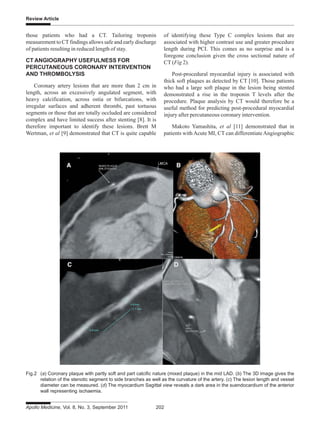

Coronary artery lesions that are more than 2 cm in

length, across an excessively angulated segment, with

heavy calcification, across ostia or bifurcations, with

irregular surfaces and adherent thrombi, past tortuous

segments or those that are totally occluded are considered

complex and have limited success after stenting [8]. It is

therefore important to identify these lesions. Brett M

Wertman, et al [9] demonstrated that CT is quite capable

of identifying these Type C complex lesions that are

associated with higher contrast use and greater procedure

length during PCI. This comes as no surprise and is a

foregone conclusion given the cross sectional nature of

CT (Fig 2).

Post-procedural myocardial injury is associated with

thick soft plaques as detected by CT [10]. Those patients

who had a large soft plaque in the lesion being stented

demonstrated a rise in the troponin T levels after the

procedure. Plaque analysis by CT would therefore be a

useful method for predicting post-procedural myocardial

injury after percutaneous coronary intervention.

Fig.2 (a) Coronary plaque with partly soft and part calcific nature (mixed plaque) in the mid LAD. (b) The 3D image gives the

relation of the stenotic segment to side branches as well as the curvature of the artery. (c) The lesion length and vessel

diameter can be measured. (d) The myocardium Sagittal view reveals a dark area in the suendocardium of the anterior

wall representing ischaemia.